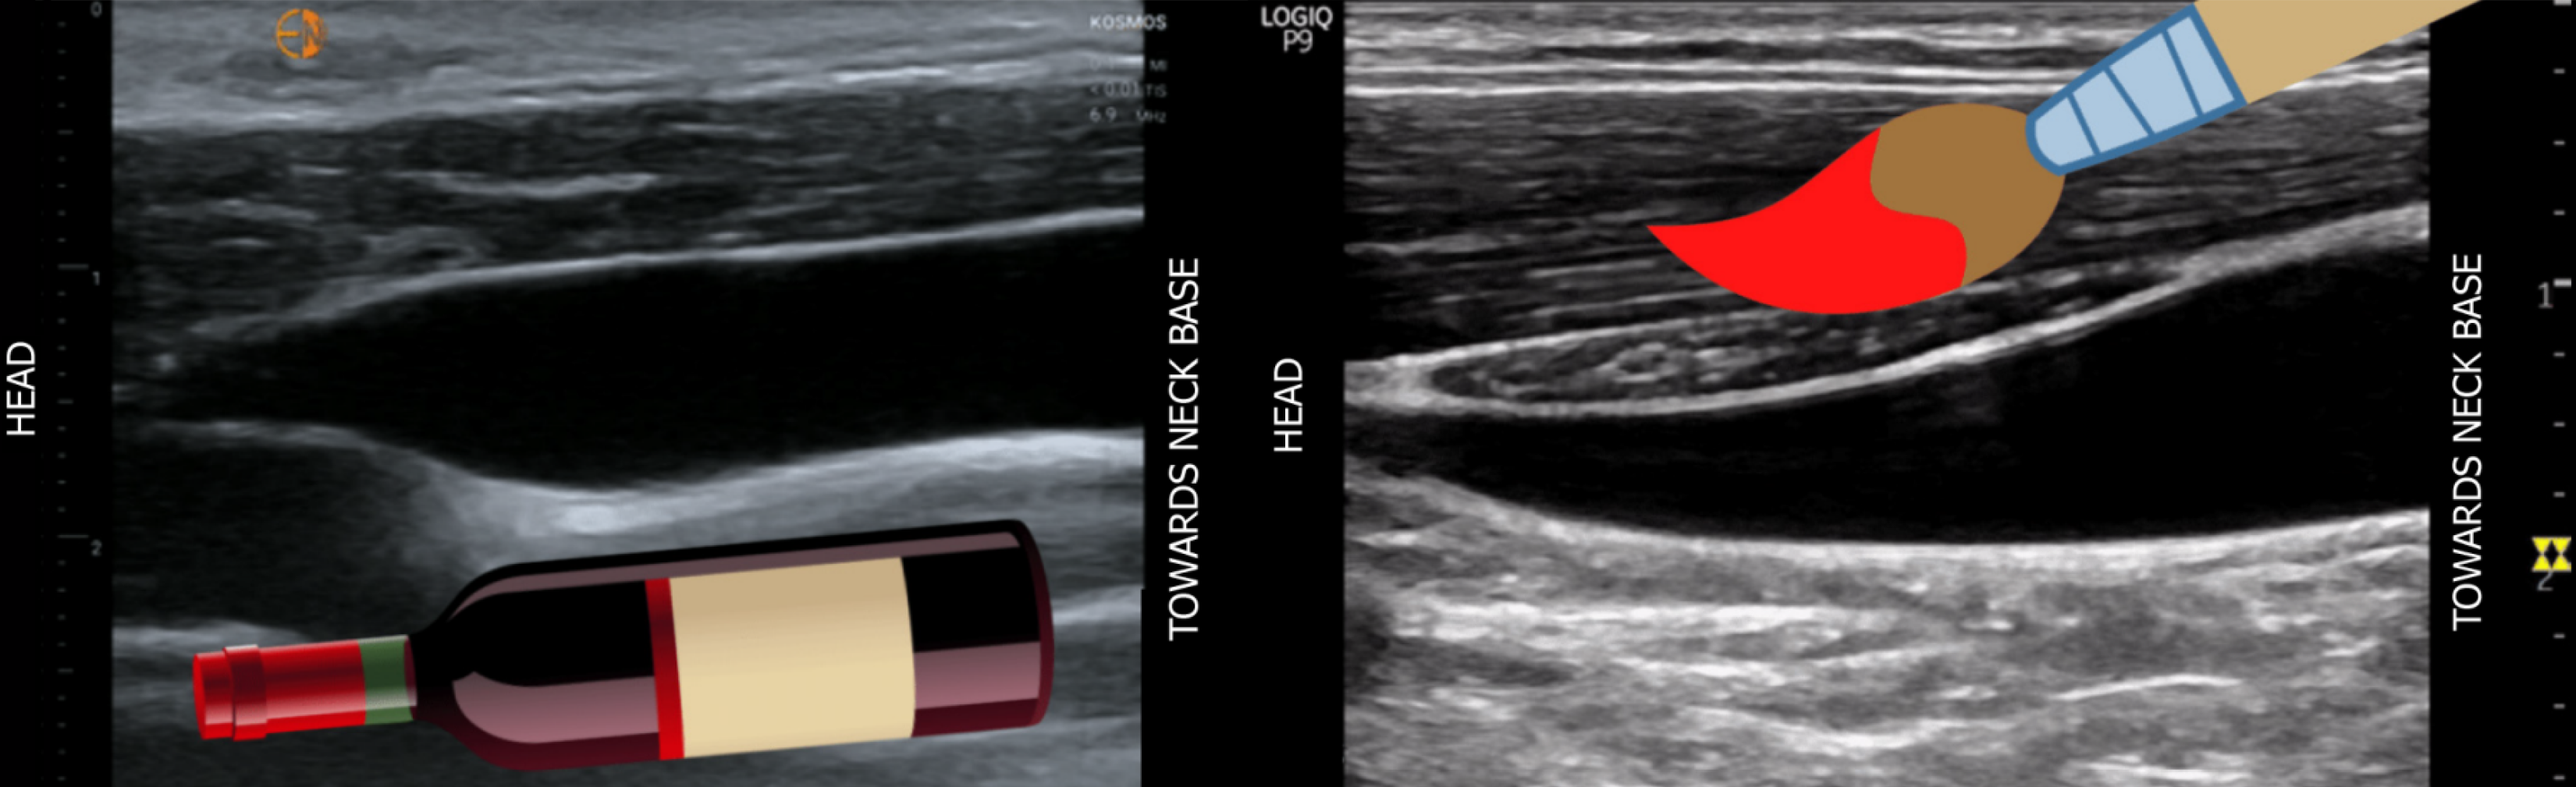

Figure 2 Long-axis ultrasound of the internal jugular vein demonstrating the collapse or taper point, often compared to a wine bottle or paintbrush.

Image reused with permission from NephroPOCUS.com. Available from: https://nephropocus.com/interesting-signs-and-metaphors/.